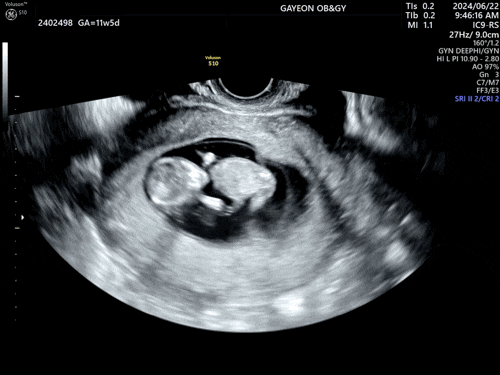

[임신12주] 1차 정밀 초음파&기형아 검사.

24년 6월 27일 떨리는 날이 다가옴. ⭐️1차 정밀 초음파+기형아 검사⭐️ (아침에 정말 별생각 다함) 예약...

[임신11주] 세 번째 산부인과 검진.

24년 6월 22일. 11주 5일 되는 날. 배가 콕콕 쑤시고 통증이 있기도 하고 지난주 추가 피검사 결과도 듣고 ...